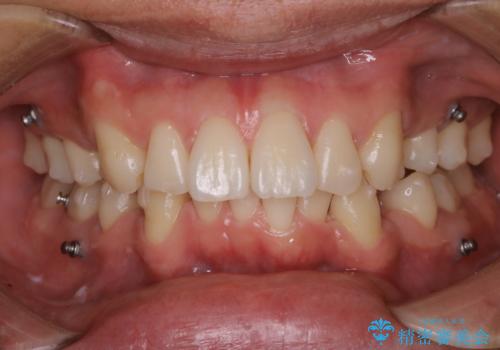

矯正中は汚れが付きやすいため、着色がとても多く付いていました。

抜歯したスペースや装置の周りの磨き方などとても難しため、定期的にクリーニングをおすすめします。